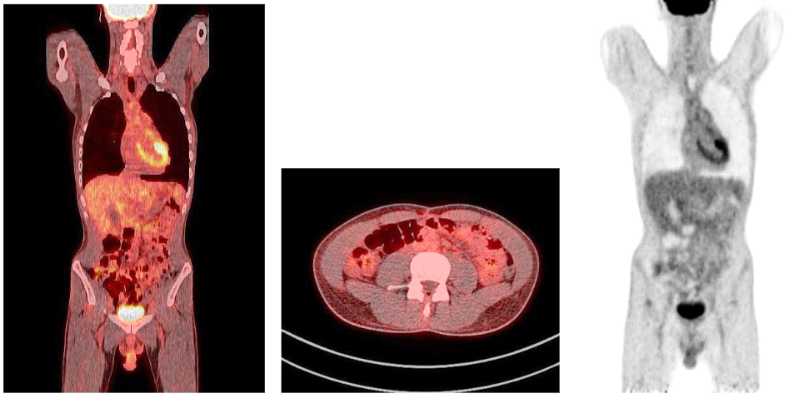

One year after the operation, a PET/ CT scan performed showed normal distribution of F-18 FDG and no signs of residual intraabdominal tumor (Figure 9). In the present period, the patient is disease free.